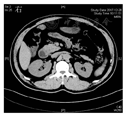

白细胞计数为8.8×109/L,嗜酸性粒细胞占0.032,血红蛋白为128 g/L,CRP为10.4 mg/L。血生物化学检查正常,ESR为19 mm/1 h。粪便隐血试验阳性,粪便钙卫蛋白为35 μg/g。自身抗体:抗核抗体阴性,血核周型抗中性粒细胞胞质抗体(peripheral anti-neutrophils cytoplasmic antibody,p-ANCA)阴性,抗酿酒酵母抗体(anti-Saccharomyces cerevisiae antibody, ASCA)阴性。结核感染T细胞斑点试验(T-cell spot of tuberculosis test,T-spot.TB)为276.5 pg/mL。肿瘤标志物阴性。2017年12月27日胃镜检查(图1)提示十二指肠降部溃疡。H.pylori阴性。2017年12月27日结肠镜检查(图2)提示回盲瓣溃疡;病理检查提示回盲瓣黏膜中度急慢性炎。2017年12月28日胃镜活组织病理检查(图3)提示黏膜重度慢性炎,间质内可见多量嗜酸性粒细胞浸润,50个/高倍视野,伴慢性溃疡,部分上皮呈低级别上皮内瘤变。免疫组织化学示CKpan(上皮+),CD68(组织细胞+),CD34(血管+),Ki-67约30%。2017年12月28日小肠CT检查(图4)显示十二指肠降部局部及水平段管壁增厚。2018年2月患者因进食困难再次行胃镜检查,病理检查提示黏膜重度慢性炎(图5)。2018年3月13日上消化道碘水造影(图6)显示十二指肠降部梗阻。2018年3月19日行剖腹探查、十二指肠狭窄成型、胃造口术,术中发现十二指肠降部和水平部交界处有一瘢痕性狭窄病灶,并与横结肠系膜有局灶性致密粘连,游离此处粘连后即可完全内翻十二指肠和胰头。十二指肠降部和水平部狭窄处宽约0.5 cm,近似完全向心性缩窄,狭窄远、近端肠管均质软,充盈良好,未见明显肿瘤样改变。术中快速病理检查提示:① 可见十二指肠组织、血管、纤维及脂肪组织,灶性见严重挤压变形的淋巴样;② 腹膜后淋巴结反应性增生。考虑良性疾病可能。术后病理检查(图7)显示:十二指肠黏膜肿物黏膜内及黏膜下层有异型肿瘤细胞弥漫浸润,核型不规则,伴绒毛萎缩。免疫组织化学检查(图8A至图8C)显示:CD3阳性,CD4阴性,CD8阴性,CD56阳性。T细胞受体基因重排检测阳性,EB病毒编码核糖核酸(Epstein-Barr virus-encoded RNA,EBER)原位杂交与免疫组织化学双重染色法阴性(图8D),考虑为单形性嗜上皮性小肠T细胞淋巴瘤(monomorphic epitheliotropic intestinal T-cell lymphoma, MEITL),相当于原WHO分类EATLⅡ型。

影像科周长圣主治医师:此例患者在十二指肠降部出现深大溃疡并出现肠腔狭窄及梗阻,影像学方面与小肠腺癌难以鉴别。小肠淋巴瘤的病变肠管可呈不规则增厚,会导致肠管环形不规则狭窄。小肠淋巴瘤好发于小肠远端,病变肠管一般能保持一定程度的柔软度和扩张度,很少出现肠腔狭窄及梗阻,病灶一般较光滑,肠腔周围的脂肪层常存在,其特征性表现为受累的肠管呈"动脉瘤样"扩张[9]。在影像学方面需要与小肠腺癌相鉴别,小肠腺癌好发于小肠近端,管壁形态较僵硬,管腔易出现向心性狭窄,且小肠腺癌边缘多不规则,会向周围方向表现出浸润性生长。CD多累及小肠,病变多呈节段性分布,孤立性的深大溃疡较为罕见,且CD急性期可出现肠壁增厚,黏膜下水肿,严重时可表现为分层样表现或"靶征",此外可伴有小肠系膜血管纠集增多,呈典型的小肠系膜"尺梳征"[10]。此例患者出现十二指肠降部孤立性溃疡,且无明显"尺梳征"等CD典型CT检查表现,需进一步手术以明确溃疡性质,确定下一步治疗方案。